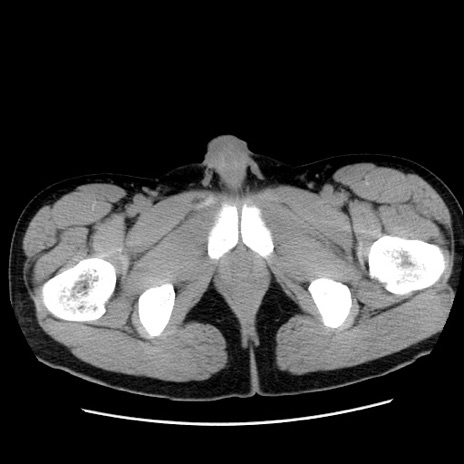

冠状断像

【症例】20歳代 男性

【主訴】心窩部痛

【現病歴】今朝より上腹部痛あり。一旦軽快していたが再度出現したため救急要請。昨日夕に白身の魚を含む刺身を食べた。

【身体所見】BP 136/89mmHg、HR 74/min、BT 37.0℃、腹部:膨満、軟、心窩部に圧痛あり。反跳痛なし、筋性防御なし、腸雑音やや亢進あり。

【データ】WBC 17700、CRP 0.48